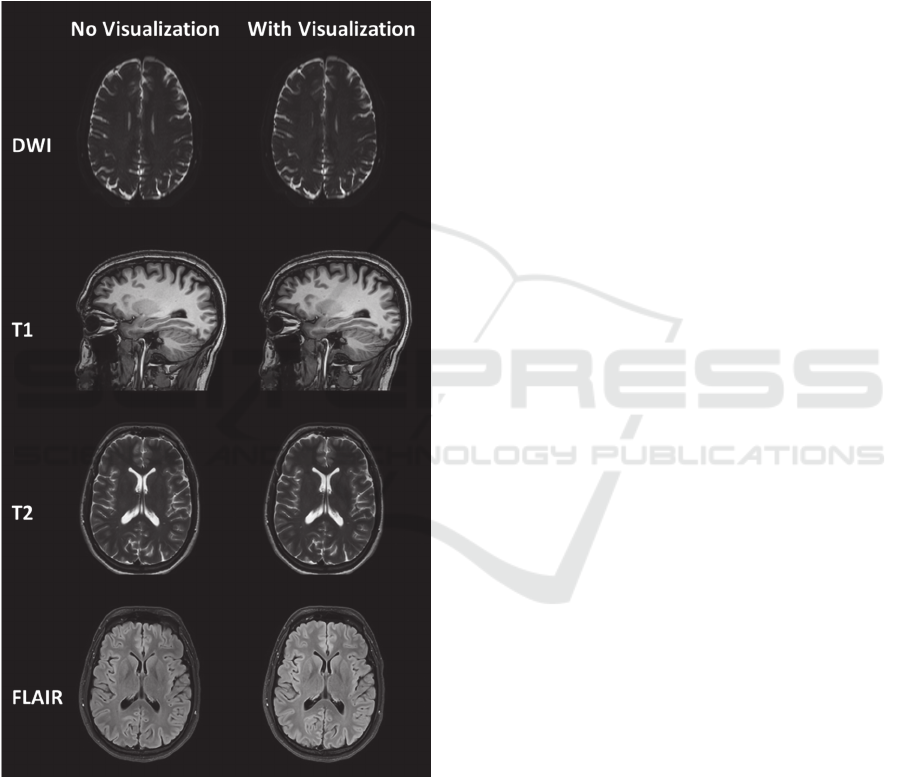

The images acquired in the two sessions (with

and without running the visualization) showed no

noticeable differences, indicating that the

visualization feedback did not affect the image

quality (Fig. 3). In one subject, motion artifacts were

observed on the dual echo scan as a result of patient

Figure 3: MRI images acquired from one volunteer with

and without the visualization. No differences in image

quality are observed between the two datasets.